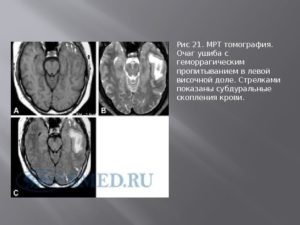

- В случае глиоза, обычно в заключении МРТ может быть написано – «картина очага глиоза в левой (правой) лобной доли».

- Если очаги множественные, то данная методика выявит все места их локализации и масштабы гибели нейронов.

- Также магнитно-резонансный томограф определит причину возникновения таких очагов.

- Если виновником отмирания нервных клеток стало заболевание сосудистого характера, то в заключении МРТ будет написано – «картина единичного (множественных) очагов глиоза в белом веществе головного мозга – вероятно, сосудистого генеза». Подробнее о сосудистом генезе головного мозга и что это такое читайте в нашей аналогичной статье.

- Кроме того, специалист может выявить дополнительные отклонения в головном мозге, в виде гидроцефалии, гематом и других болезней.